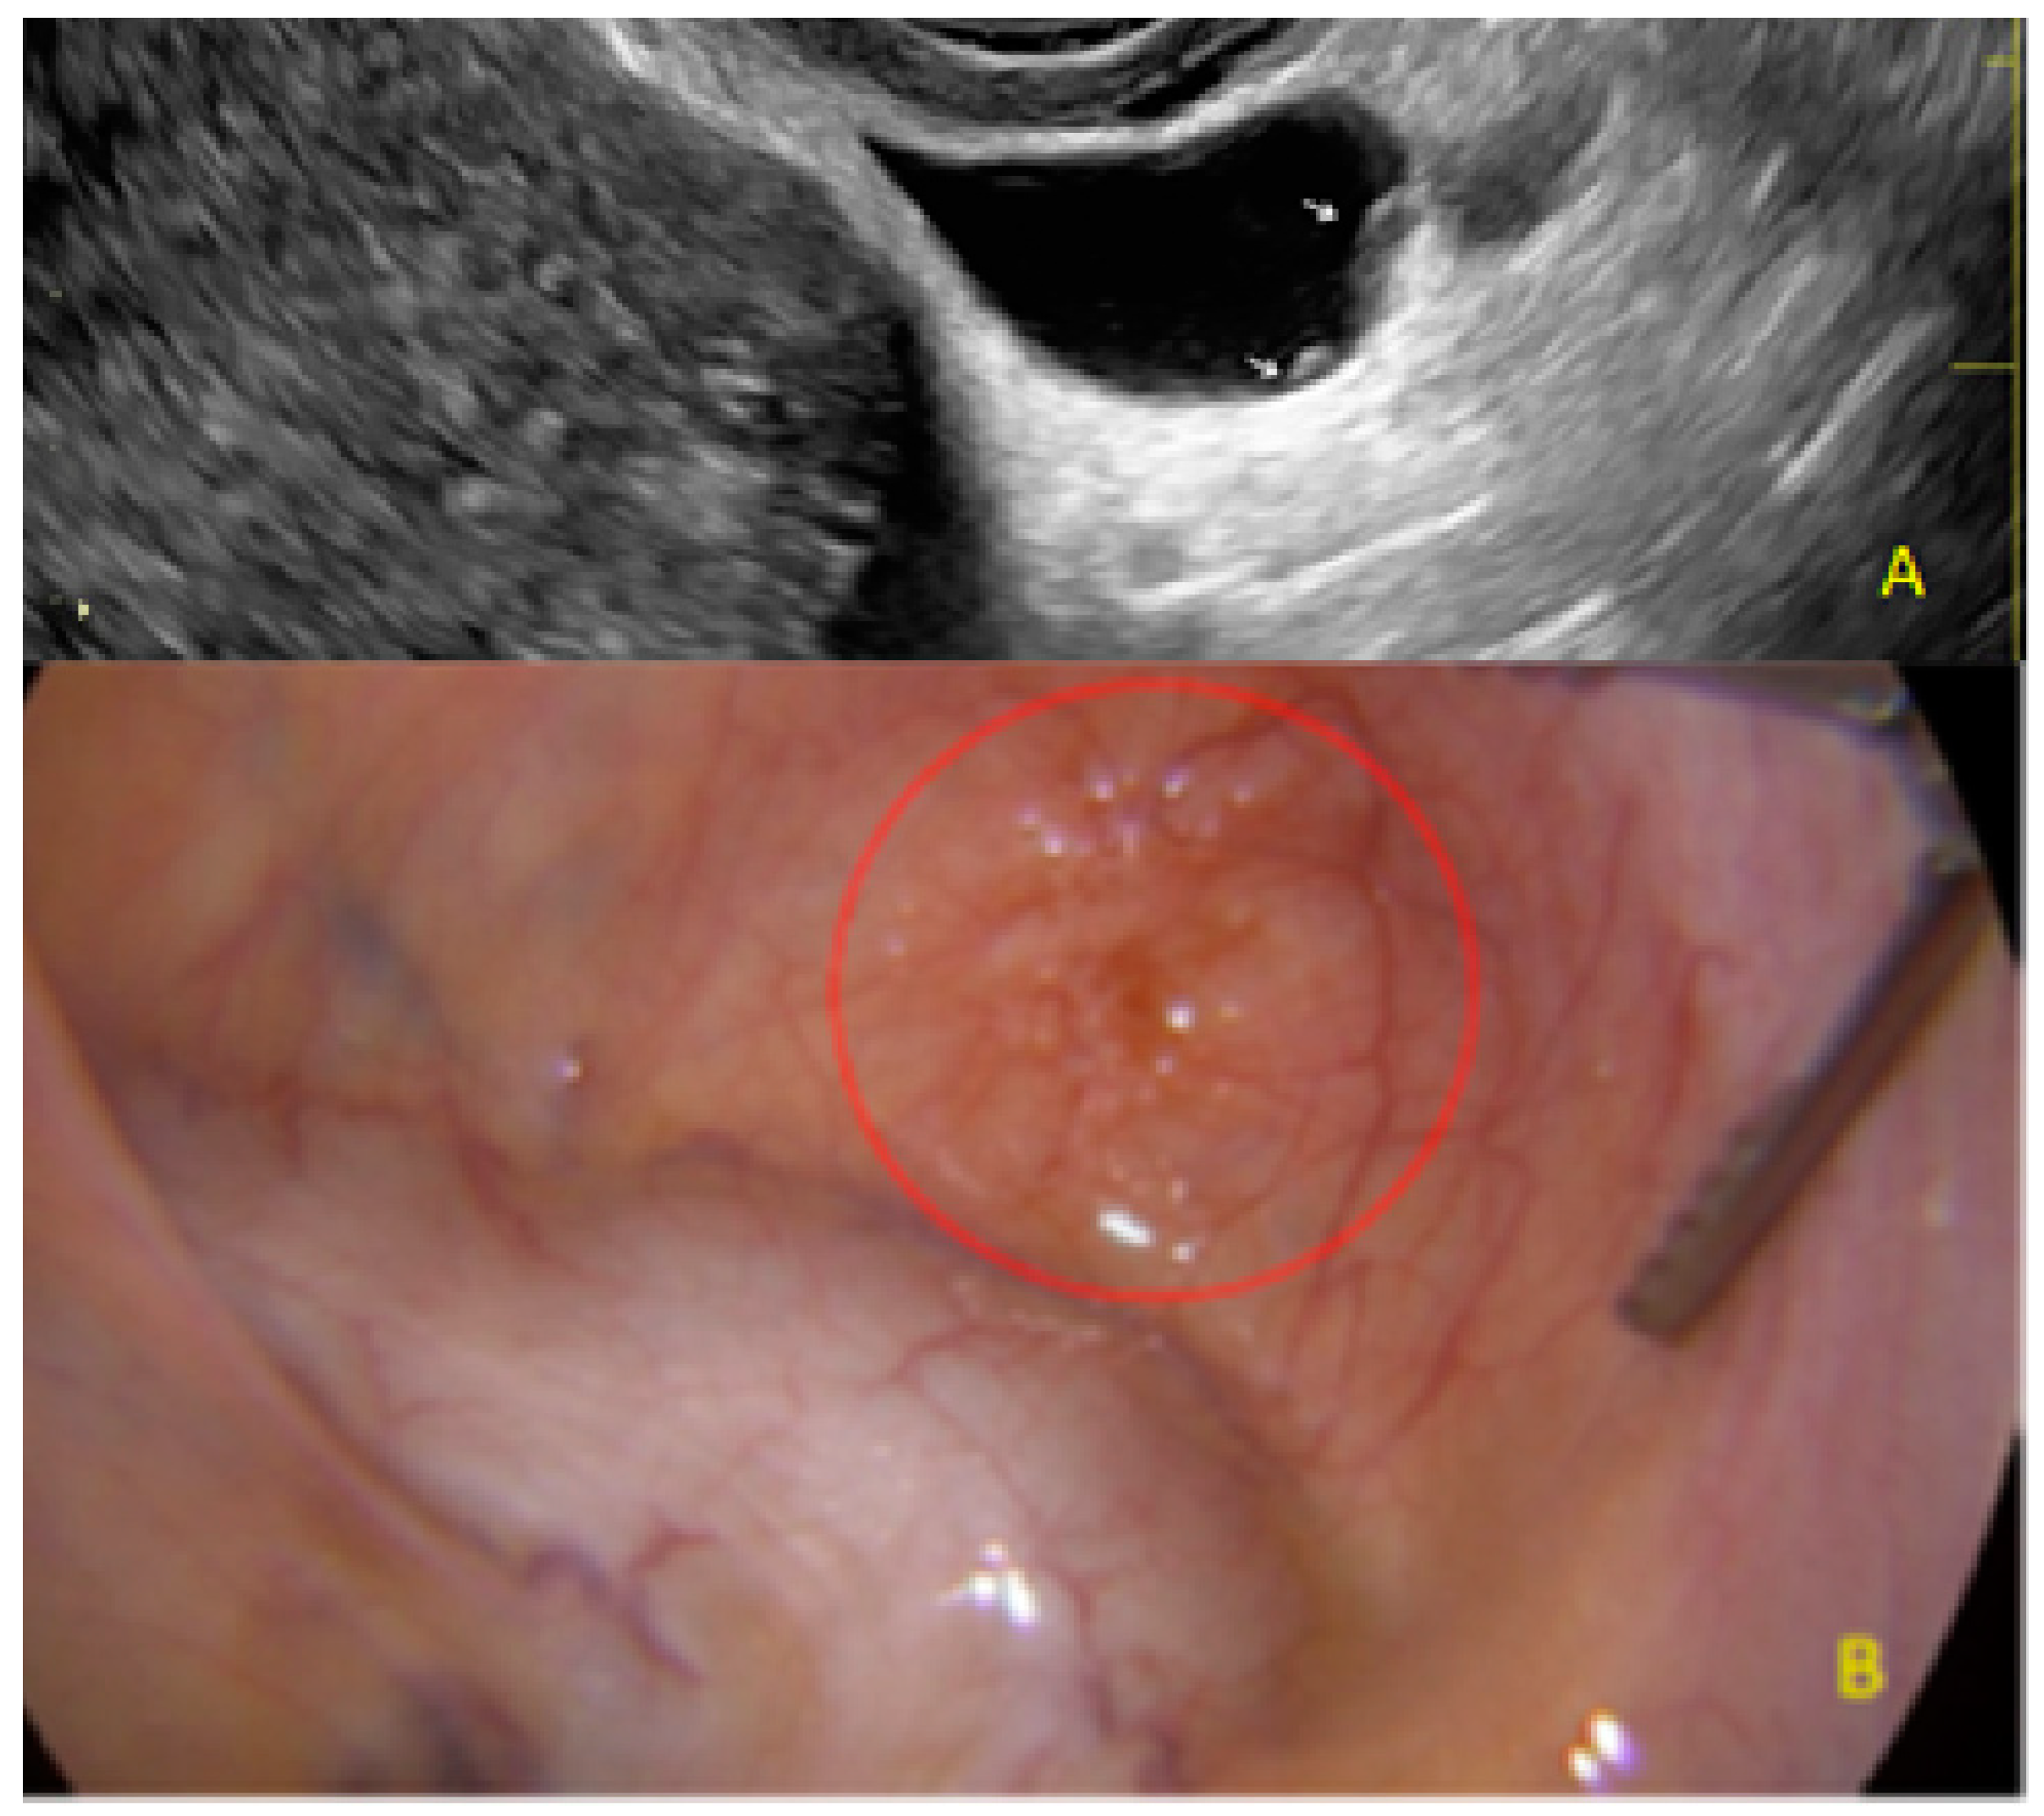

3.3. Cystic Lesions Arranged in a Cluster

- The presence of hypoechogenic associated tissue (hypoechoic areas surrounding a small cyst area; we called this a “hat”). This tissue does not protrude or invaginate the peritoneal surface.

- The presence of hyperechoic foci (we called this a “pearl”).